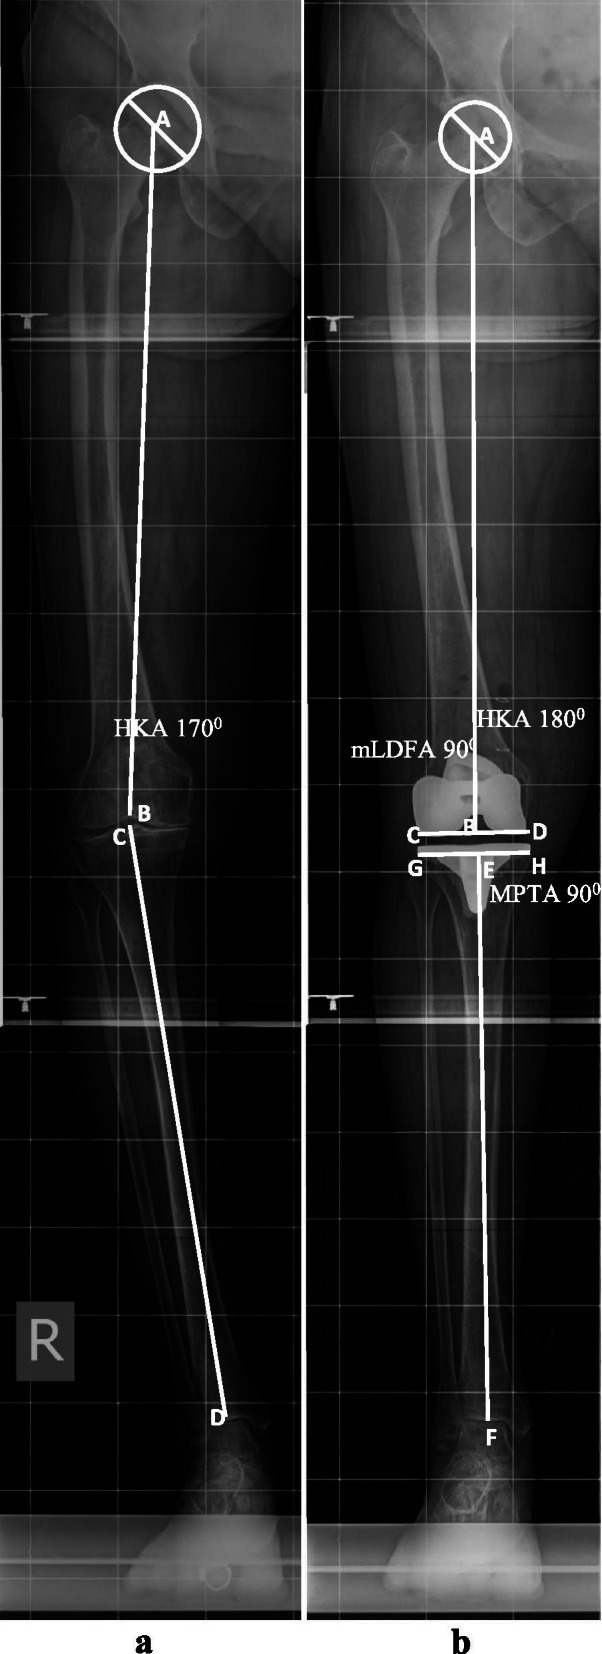

a Preoperative standing LLR denoting the centre of femoral head (point A), centre of the distal femoral articular surface (point B), femoral mechanical axis (Line AB), centre of the proximal tibia/centre of tibial spine (point C), centre of the distal tibial articular surface, coinciding with midtalar groove (point D), HKA angle i.e. angle between line AB and CD is 168° or 12° varus. b Postoperative standing LLR denoting HKA angle, (angle between line AB and EF) 180°, mLDFA, angle ABC, 90° and MPTA, angle FEH, 90°